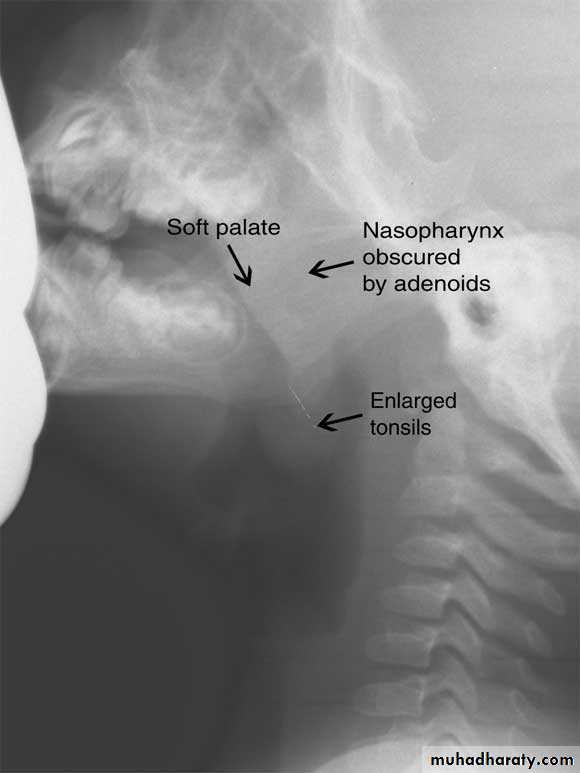

Radiography:Plain films like lateral X-Ray of the skull, is needed in nasopharyngeal mass like adenoids, and can demonstrate bone erosion in cases of nasopharyngeal cancer.

Adenoids

The adenoids lie between the roof and posterior wall of the nasopharynx.

Adenoids differ from tonsillar tissue in that it's bounded by no capsule, contains no crypts and covered by ciliated epithelium.Hypertrophy of the nasopharyngeal tonsil, sufficient to produce symptoms, most commonly between 3-7 years of age.

3. Posterior rhinoscopy and fibroptic endoscopy: lobulated mass, which occasionally extends laterally.Investigations

X-ray of the postnasal spaceComplications